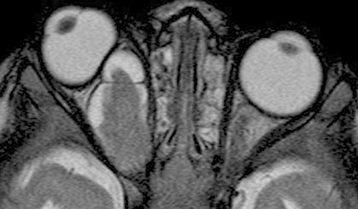

Figure 13.11.2: Right optic nerve glioma.

Rapuano9781975243722-ch013_f006.jpg

2. MRI of the brain and orbits only if indicated by a sign or symptom, including ophthalmic findings of optic nerve dysfunction, optic nerve pallor/swelling/shunt vessels, or proptosis.